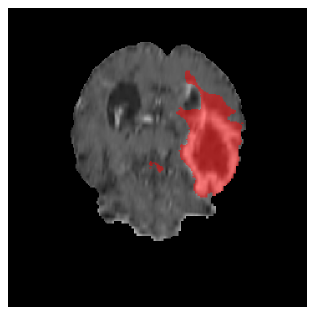

Appendix A Qualitative results

Figures 4 and 5 present the segmentation results for a patient from the BRATS dataset, visualized on a randomly selected slice. Figure 4 illustrates how tumor segmentation evolves over multiple episodes in S1 across different approaches including cumulative, naive, our approach, and the best buffer-free strategy (SI, =2). The cumulative approach, which trains on all encountered datasets together, maintains segmentation consistency across episodes but introduces significant amounts of false positives, particularly in the upper left area of the brain images. These misclassifications highlight its inability to generalize well across datasets despite access to all previous data. The naive approach, which learns sequentially without any continual learning strategy, suffers from severe catastrophic forgetting. While it initially segments well, performance deteriorates over episodes, leading to a near-complete loss of segmentation capability by the final episode. The SI (=2) approach, a regularization-based buffer-free CL strategy, performs reasonably well in early episodes but shows a significant performance decline over time. By the last episode, much of the tumor was no longer segmented, indicating difficulty in retaining prior knowledge. In contrast, our proposed approach initially produces more false positives but progressively refines its segmentation. By the final episode, it accurately retains the tumor region while minimizing misclassifications, demonstrating strong knowledge retention and adaptability across episodes. This suggests that our approach effectively mitigates catastrophic forgetting while maintaining segmentation performance over sequential learning.